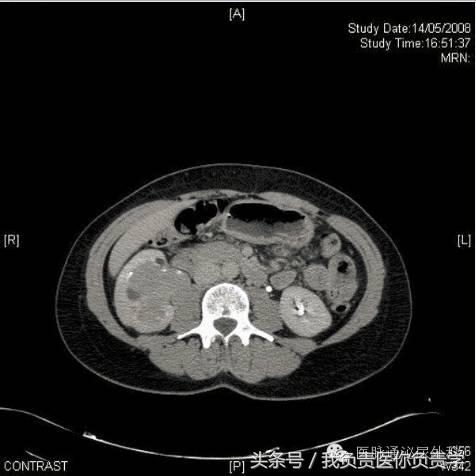

实验室分析(完整血细胞计数、凝血研究和基本代谢检查)显示血红蛋白水平和血小板计数正常,无凝血病。未发现电解质异常。尿液试纸测试未观察到血尿,尿培养阴性。尿细胞学检查对恶性细胞呈阳性。进行膀胱镜检查,显示尿道正常,膀胱由正常粘膜覆盖,未见外生性病变和活动性出血。腹部和盆骨静脉造影CT如图1。

图1

CT尿路造影的轴向图像以及相关的矢状重建,显示右肾盂中存在大面积充盈缺损。充盈缺损延伸并占据右肾盂中多数空间,造成肾造影显影期质量效应和肾脏增强的相对延迟(图2,3)。放射学表现和无痛性血尿及尿液细胞学阳性共同指示上尿路上皮癌。

在该病例中,经患者同意进行了膀胱镜检查,结果显示膀胱正常,未见任何外生肿瘤。CT尿路造影时发现右肾盂中的大面积充盈缺损结合尿细胞学检查阳性,将该患者确诊为上尿路上皮癌。